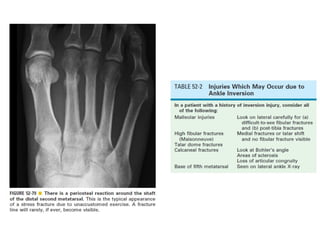

Skeletal trauma was presented by Dr Laith Fadhel with reference to Grainger's Diagnostic Radiology textbook. The presentation covered skeletal trauma as assessed through diagnostic radiology techniques. Key findings and treatments for skeletal injuries were likely discussed.